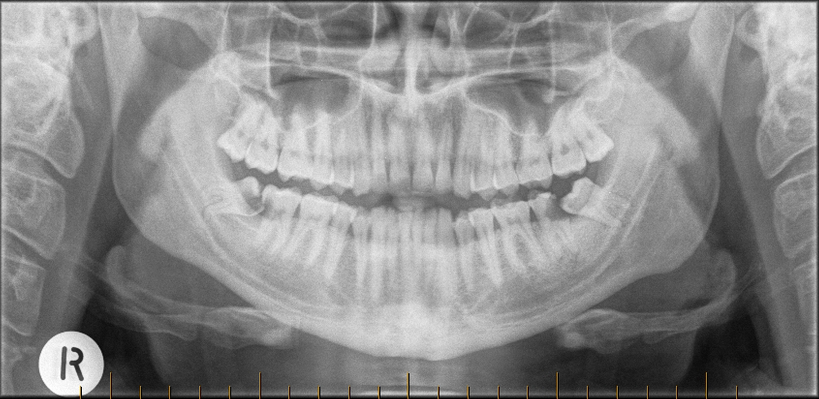

Usually removal of impacted wisdom teeth is the best solution to reduce the risk of infection, pain and risk to the other teeth. Even when wisdom teeth are not causing symptoms, examination and x-rays often show early damage and removal is recommended to reduce the risk of future problems.